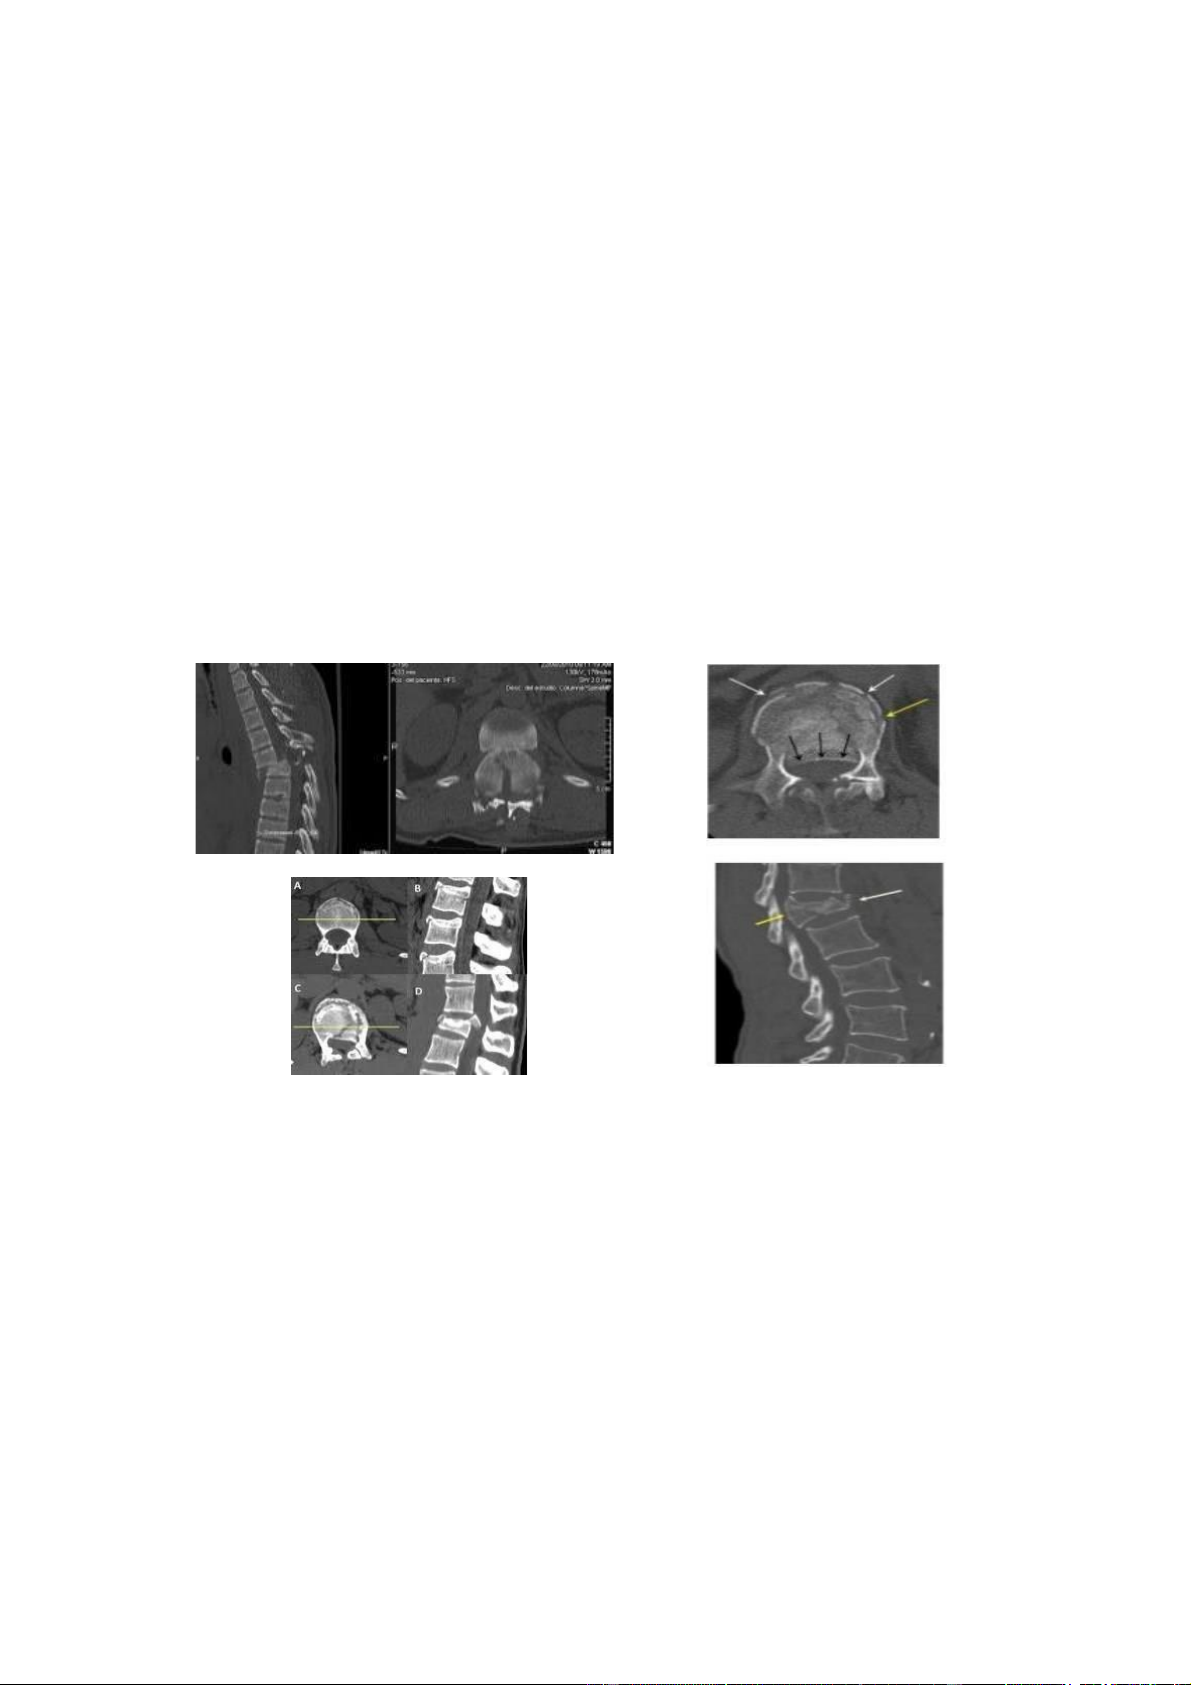

• Chụp cắt lớp vi tính

Vị trí chỉ ịnh chụp cắt lớp ược xác ịnh trên lâm sàng (ranh giới vùng rối loạn cảm

giác với vùng bình thường) và trên hình ảnh nghi ngờ của X - quang qui ước.

Trên cửa sổ xương, cho phép ánh giá, phân tích chi tiết thương tổn xương, ường

vỡ, mảnh xương vỡ, các tổn thương mỏm gai, mỏm khớp, lỗ tiếp hợp, cung sau ể xác

ịnh tình trạng mất vững; hình ảnh chèn ép ống tủy do các mảnh xương và ĩa ệm.

Tái tạo 2 và 3 bình diện cần ánh giá:

- Các gập góc, di lệch và trượt oạn trên so với oạn dưới.

- Các hẹp ống sống do sự di dời của mảnh xương.

- Các trật khớp và gãy mỏm khớp.

Dựa vào hình ảnh chụp cắt lớp ể phân loại (theo Denis). • Chụp cộng hưởng từ Để xác ịnh ược chính xác và trực tiếp thương